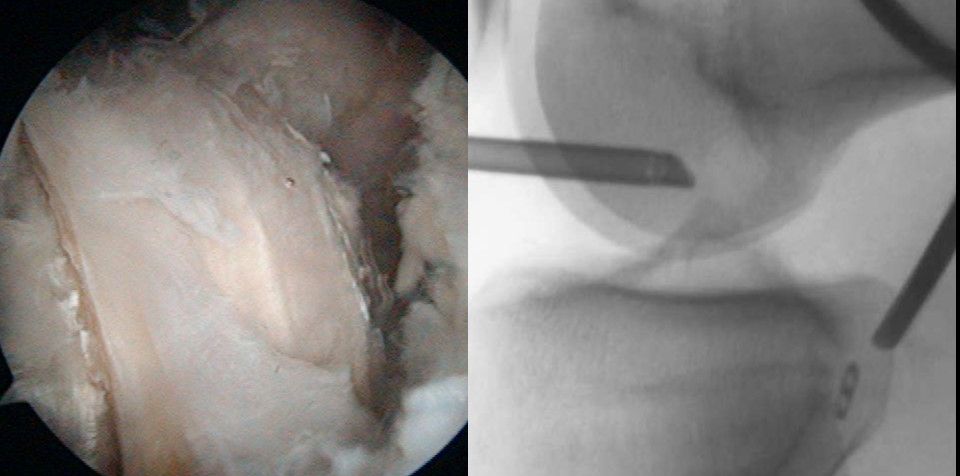

Now the retrodrill guide system with the 12mm cutter from anterior is brought in and the position of the cutter is controlled by lateral view under fluoroscopy (Fig 19).

Fig 19 - Arthroscopic view – 70° scope and fluoroscopic control